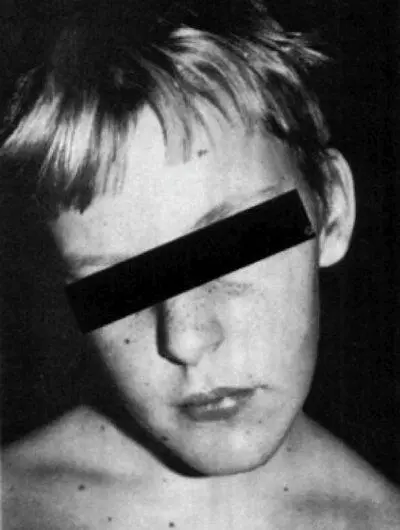

Подавляющее большинство авторов не уделяют особого внимания особенностям клинической картины детей с острой кривошеей. В иностранной литературе превалирует понятие «cock-robin position», включающее в себя фиксированный боковой наклон головы и ее поворот в противоположную сторону с невозможностью движений в сторону болей. При этом на иллюстрации пациента основоположников трактовки острой кривошеи как острого атланто-аксиального подвывиха Fielding et Hawkins (1977) практически отсутствует ротационный компонент, тем более с поворотом в противоположную от наклона сторону (рис. 6.1) [1].

Рис. 6.1.Иллюстрация ребенка с острой кривошеей [1]. Типичная для ротационной фиксации позиция «дрозда» (cock robin) с наклоном в одну сторону поворотом головы в противоположную и легким сгибанием